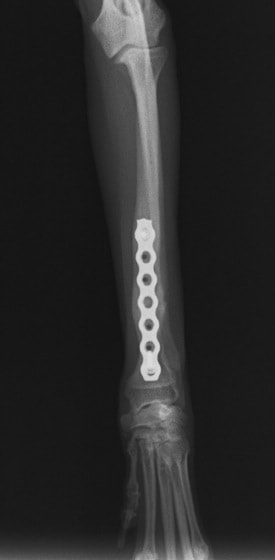

当院ではAdvanced Locking plate system(ALPS)と、Locking compression plate system(LCPS)という骨接合法で骨折症例の治療を行っています。

LCPは、スクリュー(ネジ)とプレート(金属の板)をロックする特殊な構造により骨折部位を固定する新しい世代のプレートシステムです。ひとつのホールでロッキングスクリューとスタンダードスクリューの使用を選択できるユニークな構造をしているため、骨折断端間の圧迫を目的とした従来型プレート固定法に加え、高い角度安定性を有するロッキングスクリューを用いた固定法の選択が可能です。従来のプレートシステムでは困難だった部分の骨折や癒合不全の症例に高い治療効果をもたらします。

トイプードル 右遠位橈尺骨短斜骨折のALPSによる内固定